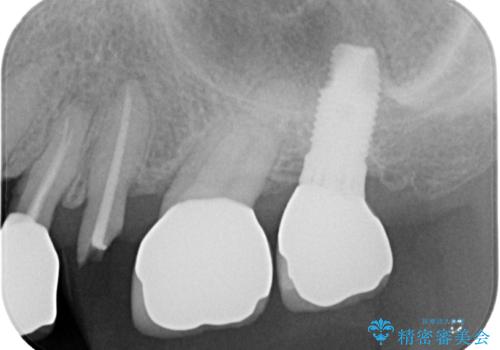

破折によりクラウンの外れてしまった奥歯 抜歯即時埋入で短期間インプラント治療

- 奥歯に装着していたクラウンが外れてしまったとのことで来院された患者様です。

診察したところ、歯根に破折線が確認され抜歯が必要な状態でした。

歯肉や歯槽骨の状態は良好であったため、抜歯即時埋入インプラントによる補綴治療を行うこととしました。